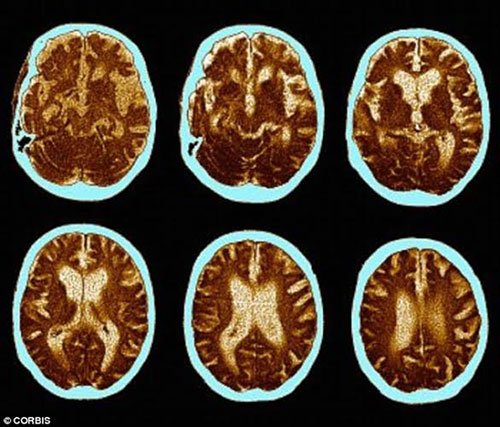

* Ngăn chặn chứng mất trí nhớ

- Chúng ta đều biết rằng sự số lượng của tế bào não tỷ lệ nghịch với số tuổi. Thực tế, khi bắt đầu bước vào tuổi 35, mỗi ngày, chúng ta mất 7.000 tế bào não. Đọc thông tin này khiến nhiều người rất lo lắng và bi quan.

- Tuy nhiên, các nhà khoa học thuộc Trường Đại học Princeton, Mỹ đã mang lại cho chúng ta một tin vui để cải thiện tình trạng này. Đó là sex thường xuyên sẽ giúp chúng ta sản sinh ra những tế bào não mới. Một nghiên cứu khác được công bố trên tạp chí PLoS ONE cũng cho biết quan hệ tình dục kích thích sự tăng trưởng của các tế bào não ở vùng hippocampus, một phần của não chịu trách nhiệm về trí nhớ và khả năng tiếp thu kiến thức.

- Các yếu tố như căng thẳng và trầm cảm có thể thu nhỏ vùng hippocampus, trong khi tập thể dục và quan hệ tình dục lại có tác dụng ngược lại.

- "Những người lớn tuổi có ít hoạt động tình dục có nguy cơ mất trí nhớ cao", Tiến sĩ Ghosh, chuyên gia về sức khỏe tình dục tại Bệnh viện Spire, Liverpool (Anh) cho biết.

- Không những thế, chuyện phòng the cũng tăng lưu lượng máu đến não, cải thiện mức độ oxy.

- "Quét não bằng kỹ thuật cộng hưởng từ (MRI) đã cho thấy đạt cực khoái giúp các tế bào thần kinh trong não hoạt động mạnh hơn và sử dụng nhiều oxy hơn", Barry Komisaruk, Giáo sư tâm lý học tại Đại học Rutgers giải thích.